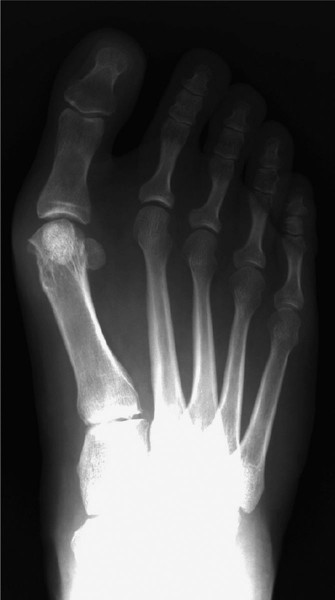

A 58-year-old woman comes to clinic reporting that her previous surgeon has performed two procedures on her f…